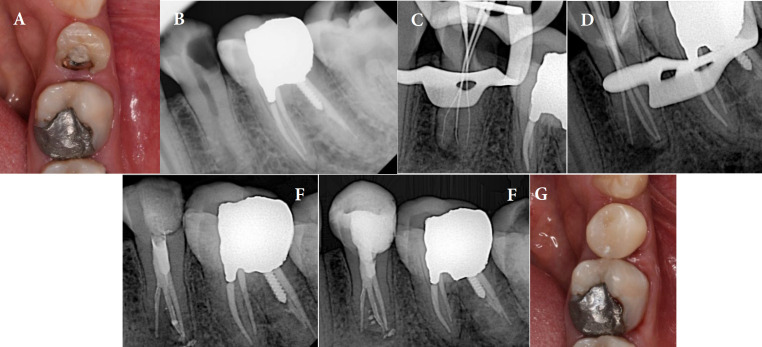

紧牙畸形是一种牙齿异常,其特征是在牙骨质-牙釉质交界处没有颈椎收缩,牙髓底顶端移位,牙髓腔扩大。由于其形态多变,根管孔深,根管系统复杂,因此对牙髓治疗提出了独特的挑战。本文报道了3例全身健康患者的高牛头牙症(牛头牙指数≈50),包括上颌第一磨牙、下颌第三磨牙和下颌第二前磨牙。锥束计算机断层扫描(CBCT)有助于诊断和治疗计划。根管治疗在牙科手术显微镜下进行,仔细探查,化学力学仪器使用旋转锉,5.25%次氯酸钠大量冲洗,温垂直封闭。12个月后,随访显示所有患者临床和影像学无症状,表明治疗成功。由于其解剖学的复杂性,剑齿虎症提出了重大的挑战。建议采用多方面的方法,包括CBCT、牙科手术显微镜、超声冲洗和温垂直封闭。这个系列的病例表明,先进的诊断辅助和细致的技术,甚至可以有效地管理高牛牙。

Taurodontism is a dental anomaly characterized by the absence of cervical constriction at the cemento-enamel junction, apical shifting of the pulpal floor, and an expanded pulp chamber. This condition presents unique challenges in endodontic diagnosis and treatment due to its variable morphology, deeply located orifices, and complex root canal system. This paper reports three cases of hypertaurodontism (Taurodont Index ≈ 50), including a maxillary first molar, mandibular third molar, and mandibular second premolar in systemically healthy patients. The identification and treatment planning were facilitated by cone-beam computed tomography (CBCT). Root canal therapy was performed under a dental operating microscope, with careful exploration, chemomechanical instrumentation using rotary files, copious irrigation with 5.25% sodium hypochlorite, and warm vertical obturation. Twelve months later, follow-up visits showed that all patients were clinically and radiographically asymptomatic, indicating successful outcomes. Taurodontism presents significant challenges due to its anatomical complexities. A multifaceted approach involving CBCT, dental operating microscopes, ultrasonic irrigation, and warm vertical obturation is recommended. This case series demonstrates that with advanced diagnostic aids and meticulous techniques, even hypertaurodontic teeth can be effectively managed.